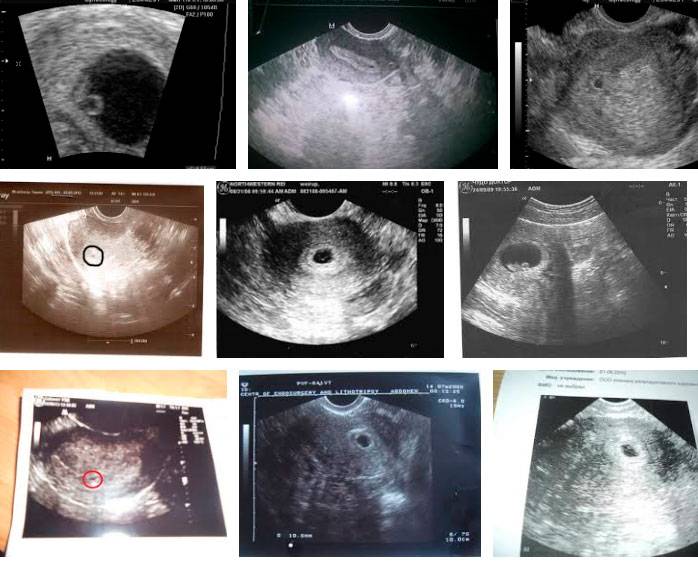

Узи на 2-ой неделе беременности плодного яйца не покажет.

Таким образом, к концу второй недели гестации имеется плодное яйцо размером примерно 1 мм со сложной дифференцированной структурой — крохотным эмбрионом, имеющим двухслойное строение (будущие ткани + органы), и тремя внезародышевыми органами — хорионом, желточным мешочком и амниотическим пузырем.

Некоторые считают сроки вынашивания с момента, когда произошло оплодотворение. Если считать сроки по этому принципу, то фактически на 2 неделе беременности от зачатия у мамочки уже 4 акушерская неделя. В этот период уже можно смело говорить о состоявшейся беременности, а при прохождении ультразвуковой диагностики – официально подтвердить ее факт.